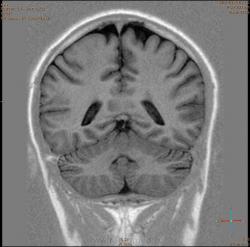

Болезнь Маркиафавы-Бигнами посмотри. На мой взгляд подходит.

Я заметил только 1 очаг в валике мозолистого тела. А для б-зни Маркиафавы-Бигнами более характерно несколько очагов дегенерации, в том числе и в полушариях.

Для болезни Маркиафава-Биньями считается патогноманичным центральная дегенерация мозолистого тела.

"Болезнь Маркиафава-Биньями – Болезнь Маркиафава-Биньями (Marchiafava, Bignami)- синдром при хроническом алкоголизме: энцефалопатия в форме центрального некроза corp.callosum (иногда и других комиссур). "

Аналогичный случай я ещё нашел в книге Diagnostic Imagic brain, кстати меня осенило только именно после чтения этой книги, потому как контроль МР-исследования я проводил где то в октябре и при сравнении динамики не мог долго понять, что это может быть:

Я не против, действительно м.б. "Болезнь Маркиафава-Биньями". Особенно если нет динамики.

Но диф. ряд должен быть с опухолью. И если есть негативная динамика, тогда больше похоже на то, что в моз.теле не дегенерация, а "плюс-ткань" - обьемное образование. За октябрь сканов нет?

К сожелению первое исследование проводил ни я, а моя коллега, но контроль был за мной. Уже при первом исследовании, опухолевую принадлежность можно взять под сомнение, по скольку, даже допустим возьмем глиобластому это злокачественная опухоль из глиального ряда, т.е. должен быть тумор+отек=масс-эффект, ни того и не другого нет, ко всему этому сама локализация это валик мозолистого тела, а ни гемисфера, компенсации ни должно быть ни какой, клиника должно быть молниеносной и нарастающей.

Ко всему выше перечисленному могу добавить, видимо мою коллегу сомнения гложили, она провела исследование с контрастированием и получила тот же результат.